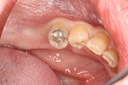

Alan Chinn #4-5 pre-op